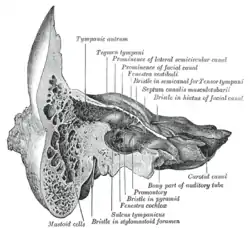

Coronal section of right temporal bone. (Mastoid cells labeled at bottom left.) | |